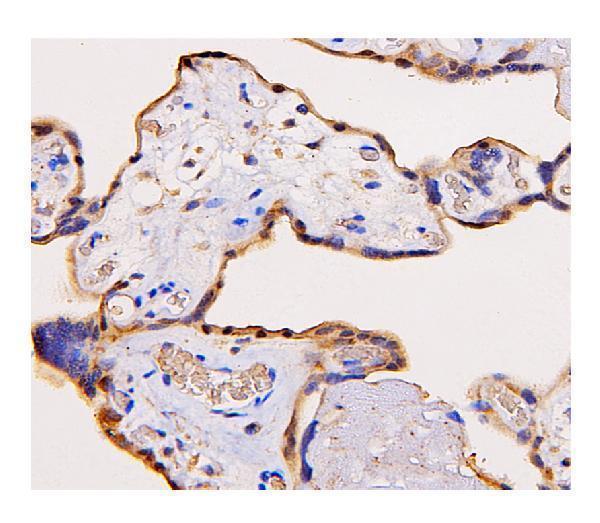

Widely expressed. Highest level in placenta, liver, muscle and kidney.